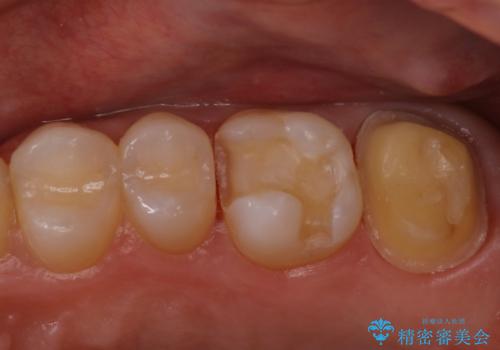

- 歯茎がよく腫れ、痛みが出ることを主訴に来院された患者様です。

レントゲン等から、金属の被せ物が歯にあって作られていないことがわかり、汚れの貯留もみられました。

金属を除去し、虫歯の治療後に型取りを行い、清掃性、審美性に優れたセラミックインレー、セラミッククラウンを装着いたしました。